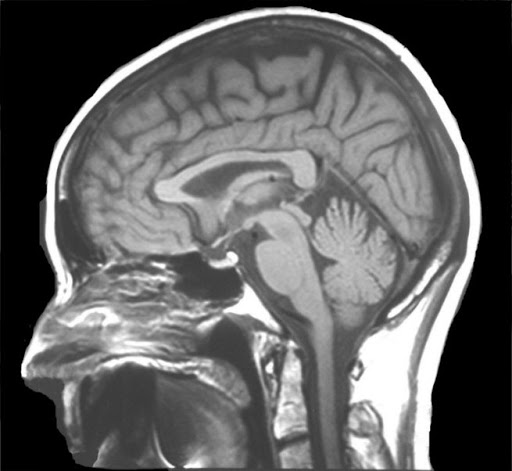

what view is this?

sagittal

which plane is shown here?